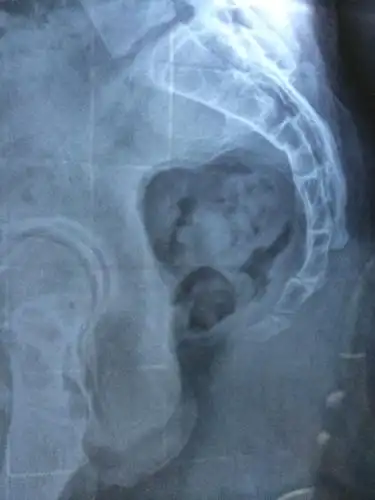

尾椎骨正常形状图片,尾椎骨骨折_大山谷图库

本院x片报告:骶椎及尾椎未见骨折与脱位征.

尾椎骨受伤,这是拍的x片,请帮忙看下严不严重?

骶尾椎影像报告怎么写

骶尾部骨折